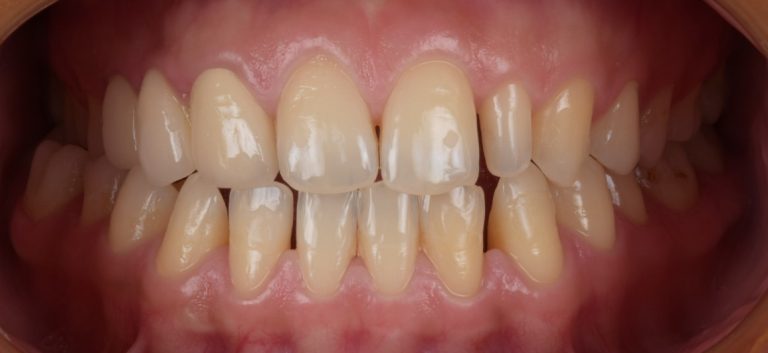

Résultats obtenus

- Relation de classe I obtenue

- Guidage fonctionnel des canines des deux côtés

- Articulé postérieur corrigé

- Surplomb et recouvrement normaux obtenus

- Surplomb amélioré

- Lignes médianes coïncidentes

- Bonne inclinaison axiale des incisives

- Courbe de Spee nivelée

- Forme de l'arcade améliorée

- Cas où tous les objectifs du traitement ont été atteints

- Des arcades harmoniques ont été obtenues

État final